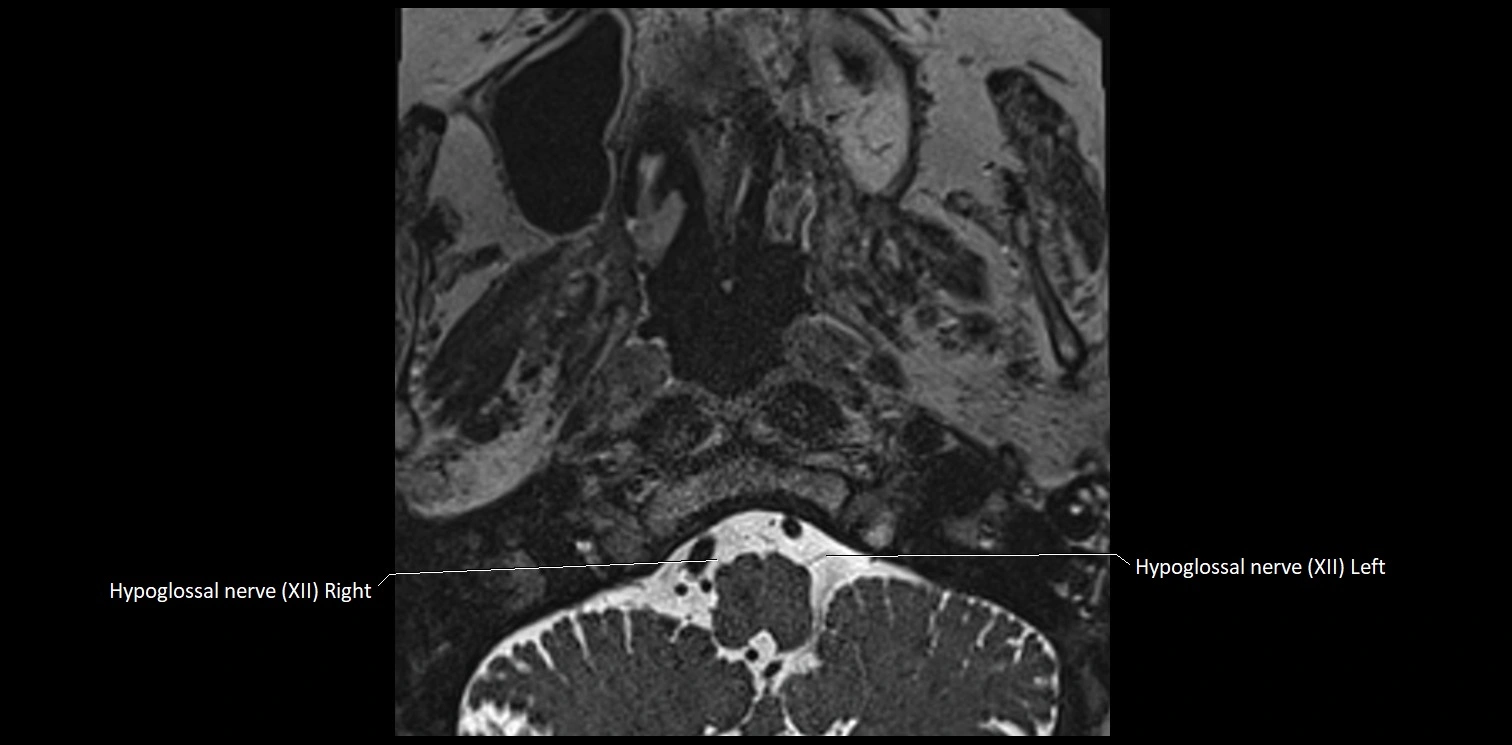

MRI Appearance

• The abducens nerve is a small, thin, linear structure

• Best visualized on high-resolution T2-weighted 3D MRI sequences (e.g., FIESTA or CISS)

• Seen as a hypointense (dark) line running from the brainstem at the pontomedullary junction, traversing the prepontine cistern, and entering Dorello’s canal under the petrosphenoidal ligament, then into the cavernous sinus, and finally the orbit

• May be challenging to visualize in standard MRI due to its small size

• Pathology may be inferred by absence, displacement, or enhancement of the nerve

MRI images

image